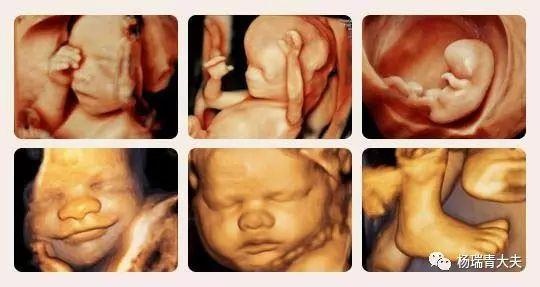

“宫内5D电影”其实就是通过5彩超实时动态地显示胎儿在子宫内的情况,先来组静态图,虽然是静态,但看得更清楚,图片也足够惟妙惟肖,必定能激发起您的想象力哦!

再看看这张动态图片,通过5D彩超,孕妈可以看到胎宝在腹中微笑、吮手指、踢腿、伸懒腰、打哈欠,通过它可以捕捉到宝宝在母体内的一举一动

怎么样,看了以上两组图片,隔着妈妈的肚皮,准妈准爸是不是已经感觉到自己的孩子真实是太可爱太淘气了,真的是迫不及待的要和宝贝见面了!